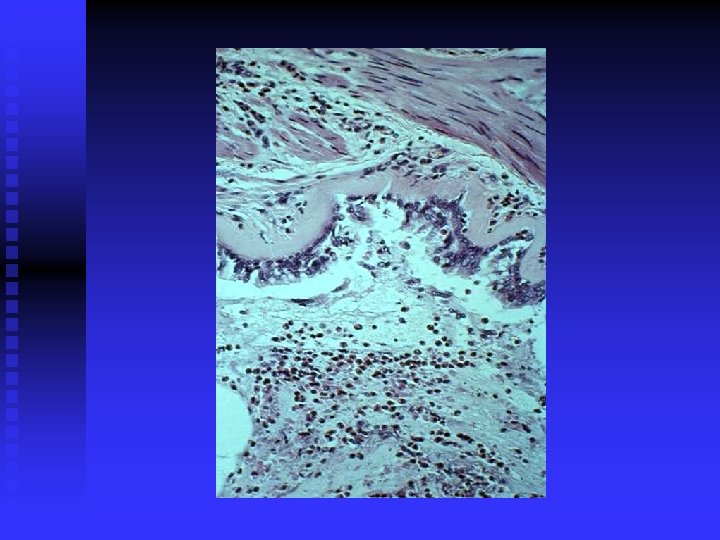

Zapalenie Ø Ø Przejawem zapalenia jest obecność pobudzonych komórek zapalnych w obrębie zajętej tkanki Rodzaj komórek zapalnych zmienia się wraz z charakterem zapalenia Nasilenie stanu zapalnego zależy od liczby komórek i stopnia ich aktywacji Komórkami zapalnymi w astmie są eozynofile, k. tuczne, limfocyty, neutrofile, makrofagi, fibroblasty

Zapalenie alergiczne Ø Złuszczanie nabłonka oskrzeli Ø Złogi kolagenu pod błoną podstawną nabłonka Ø Obrzęk błony śluzowej Ø Pobudzone mastocyty Ø Nacieki z komórek zapalnych: eozynofilów, neutrofilów, limfocytów